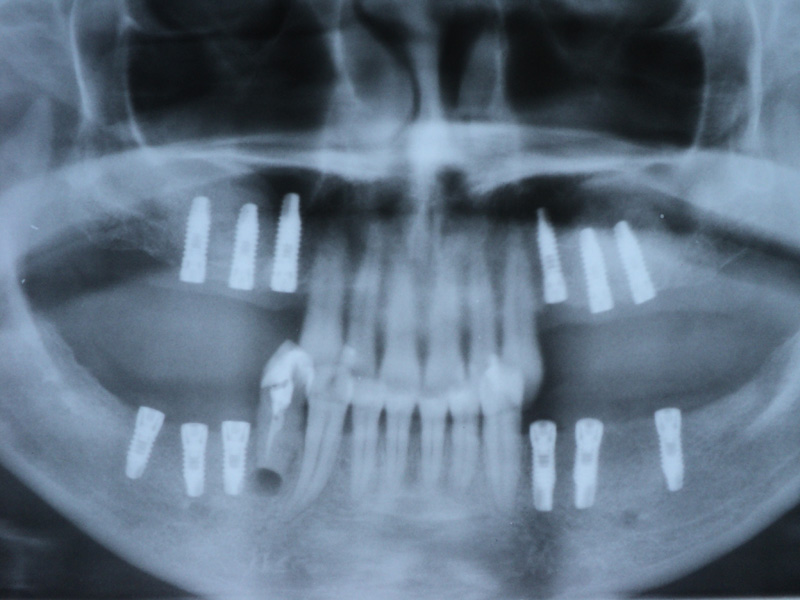

Implante - Galerie Foto

Radio-

grafii